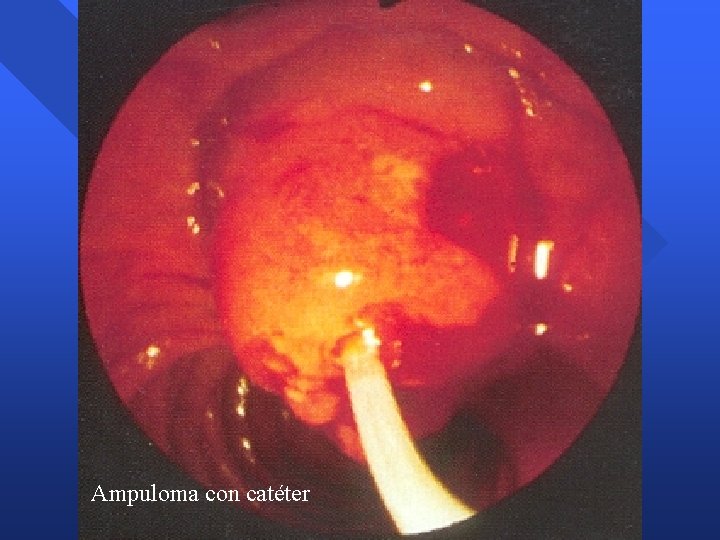

Tumores Ampolla Vater Ampuloma n Apariencia endoscópica – – – Papila mayor aumentada de tamaño Impronta suprapapilar colédoco distal dilatado Mucosa normal » Ampuloma intraductal – Mucosa neoplásica » Nodular, irregular, friable, ulcerada n Apariencia radiológica – Colédoco y conducto pancreático dilatados – Retraso evacuación drenaje – Estenosis distal / defecto repleción distal

Ampuloma con catéter